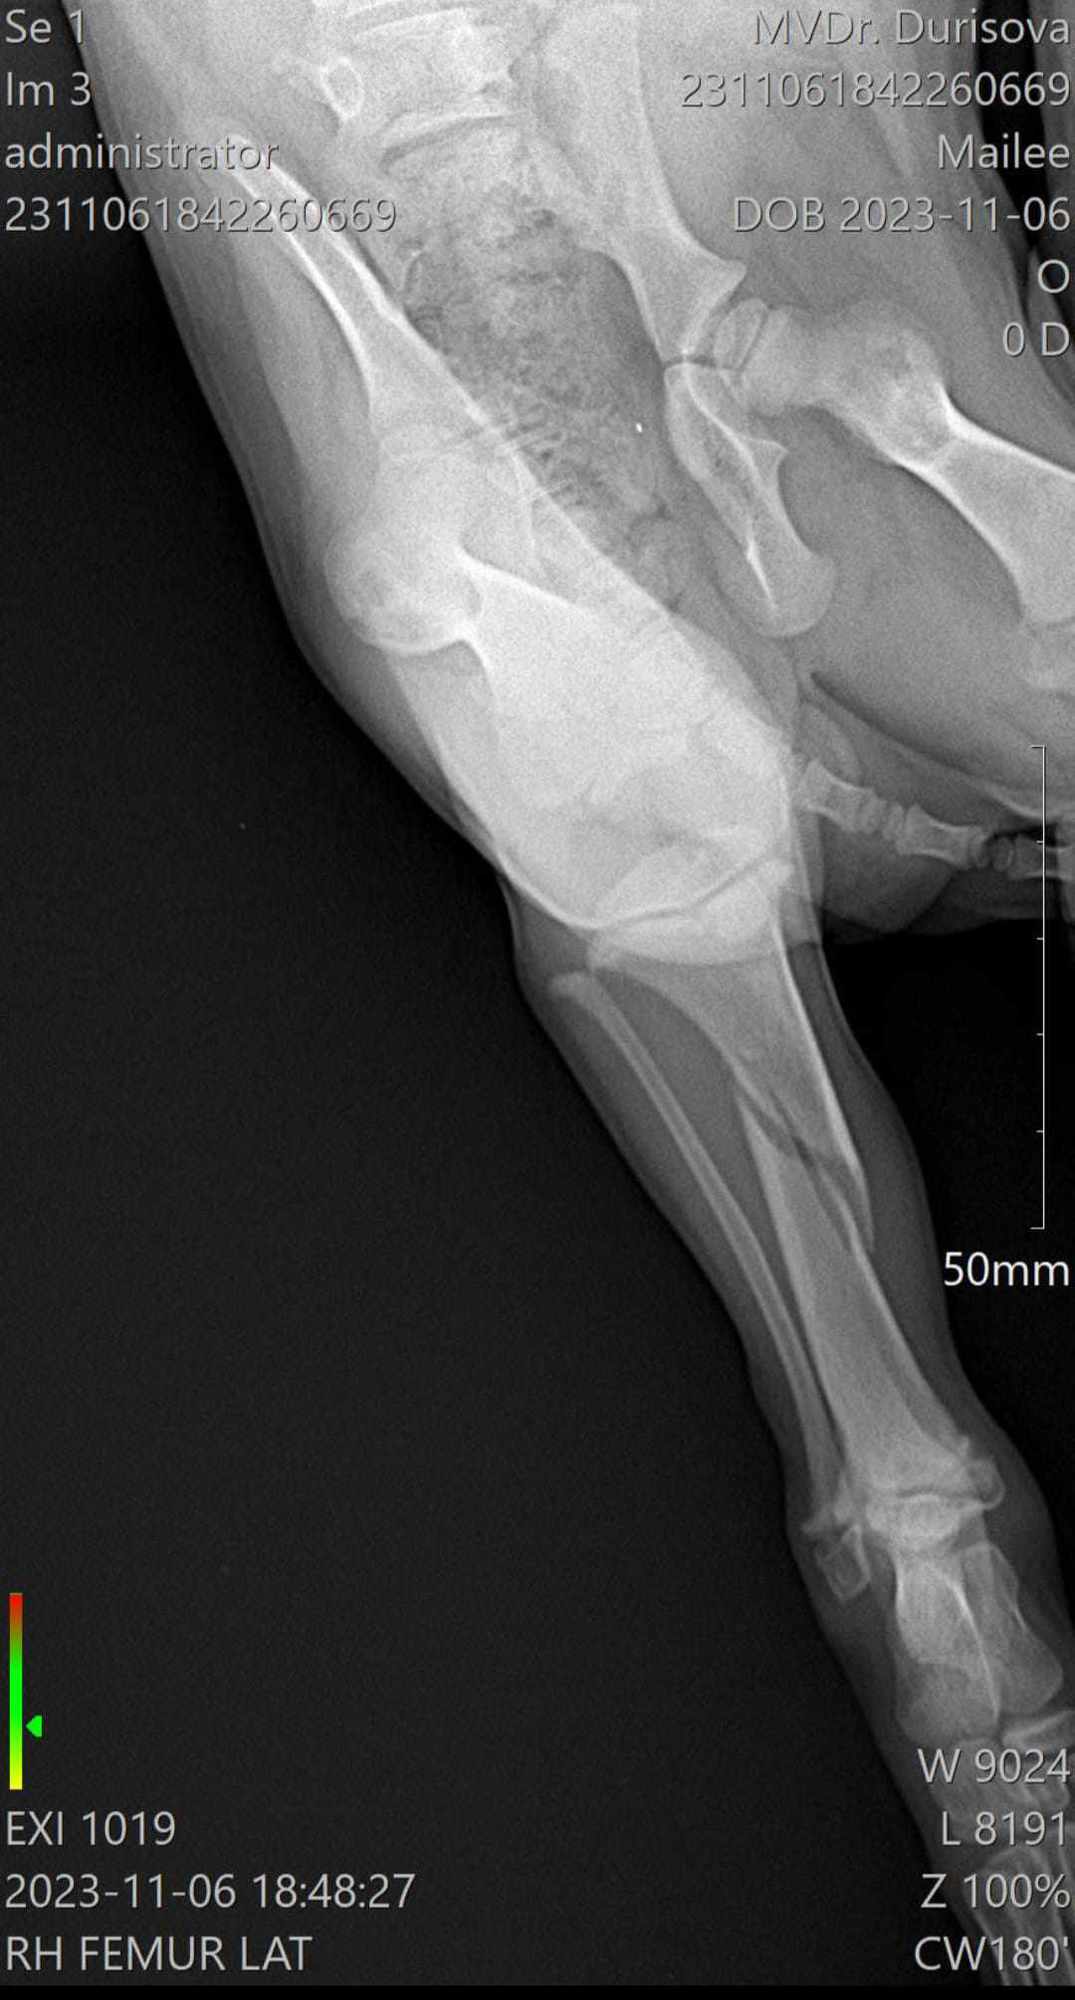

Mailee je roztomilá holčička údajně plemena welsh springer španěla. Má zlomenou zadní pravou packu. Zlomenina je spirálová , což je paradoxně ta lepší zpráva, protože by se měla dobře hojit. Podstoupila na klinice operaci, kde se zlomenina zafixovala. Mailee čekají převazy, kontrolní rentgeny a vyndání stehů. Dostává léky na bolest každý den a sirup. Po operaci hodně plakala, ale už pomalu začíná řádit. Potřebuje kontakt ostatních dvounohých i čtyřnohých společníků, protože byla brzy odstavena od maminky. Jakmile je v blízkosti psího parťáka, je klidná a usne. Dle veterináře by zlomenina měla být do dvou měsíců v pořádku a nemělo by jí to nijak v budoucnu omezovat.

• zlomená pravá zadní packa - operována